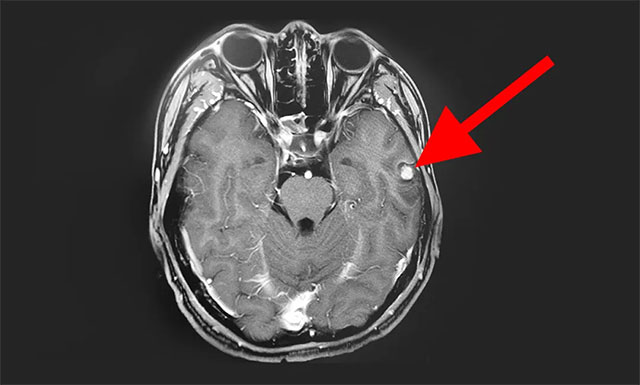

入院后,完善其各项检查,为了更好的手术,并进一步确定病灶位置,增强扫描,进行了头部MRI平扫+增强+MRS+MRSI,影像结果显示:患者左侧颞叶可见一团块状异常信号, T1WI 低信号为主,其内见结节状高信号,T2WI高信号为主,边缘低信号,FLAIR与DWI低信号为主、低混杂信号;MRS示体素位于左侧颞叶病灶,波谱基线不稳。

▲ 患者病灶位于左侧颞叶,其波谱图显示异常